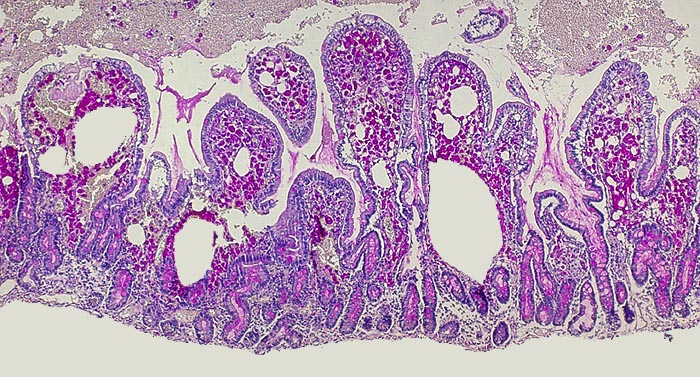

AP/ Morbus Whipple

Morbus Whipple

Entzündung infektiös

Dünndarm